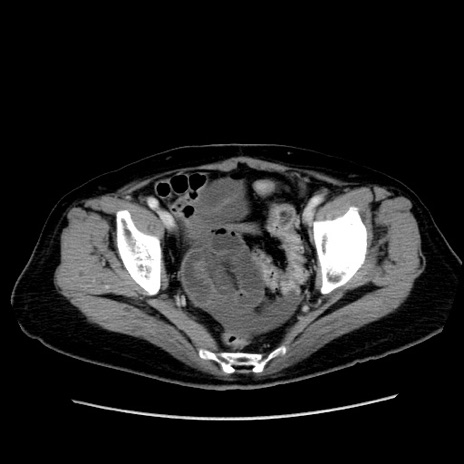

症例19(横断像)

【症例】80歳代女性

【主訴】下腹部痛

【現病歴】約8時間前より下腹部痛の出現あり、救急外来受診。

【既往歴】両側付属器切除

【身体所見】意識清明、下腹部正中に手術痕あり、その部位に一致して圧痛と反跳痛あり。腸蠕動音は亢進。

【データ】WBC 9300、CRP 0.15